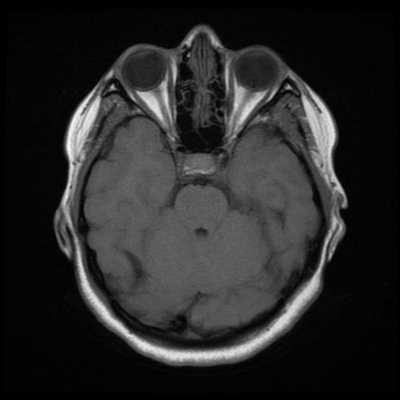

МРТ считается предпочтительным методом исследования для диагностики менингиом и их последующего наблюдения. МРТ позволяет с большой точностью обнаружить менингиомы типа en plaque или задней черепной ямки, которые легко пропустить при КТ. Исторически у КТ есть ряд ограничений в осуществлении снимков в любых других проекциях, кроме аксиальной. Тем не менее, современная спиральная КТ, или мультидетекторная КТ (МДКТ/МСКТ), позволяют значительно улучшить качество сагиттальных и корональных изображений, получаемых на основании аксиального снимка. По сравнению с МРТ, на КТ труднее различить различные варианты строения мягких тканей.

Нетипичная КТ-картина является основной причиной ошибок в предоперационной постановке диагноза. Так, могут быть пропущены менингиомы задней черепной ямки . Кроме этого, КТ не в состоянии отобразить наличие кист во внутричерепных менингиомах. Ложно-отрицательные результаты могут быть получены при наличии кистозных образований в менингиомах головного мозга. К ложно-положительным результатам могут приводить обширные зоны отложения кальция в твердой мозговой оболочке, которые могут имитировать заболевание. Снизить число ошибок, обусловленных человеческим фактором, помогает второе мнение.